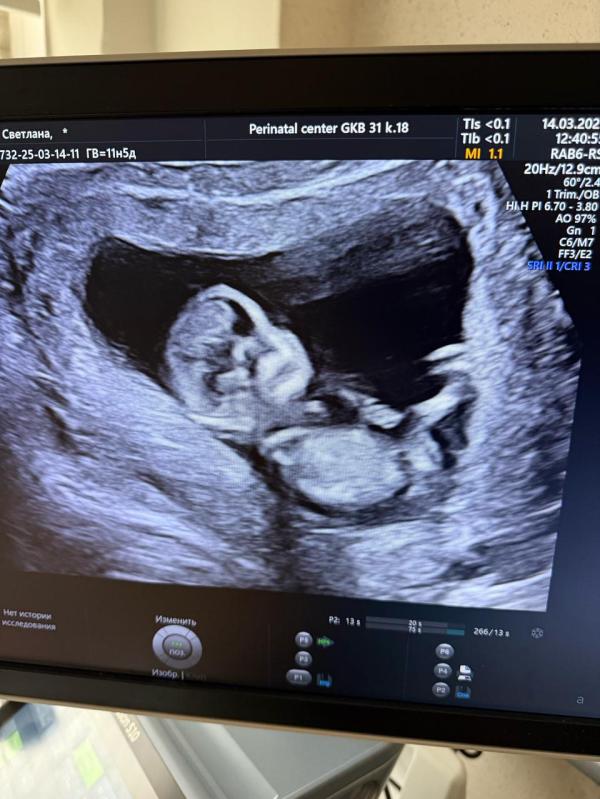

Девочки🌸 у кого есть опыт , можно предположить по фото, кого ждем? Срок по узи 12,3) врач сказала, что это не точно, но она предполагает, что мальчик🙈 третий парень🙈 я то готова, муж грустит)))

@ekaterinade, ну как знаете ) работаю уже не год и не два пренатальным диагностом) видеть можно все, что угодно) но поверьте ,иногда очевидный мальчик оказывается девочкой) на 1 скрининге. Да мы можем почти на 90 процентов озвучить пол при идеальном положении плода - но никак не потому что видим половые губы или половой член )

@gdzhst, а по каким тогда признакам озвучивается пол ??? Я конечно понимаю , что на этом сроке видно «половой бугорок» а не полностью развитые половые органы…но ведь исходя из его внешнего вида и делается предположение , не так ли?

@ekaterinade, исключительно исходя из его наклона. Который при несколько косом положении плода, либо если он слишком согнут - может быть не очень достоверным. Иногда я вижу у меня плод лежит идеально, я озвучиваю сразу что я практически уверена , но иногда бывали случаи когда кажется что мальчик , при этом я понимаю что плод лежит ну так себе) , а потом к концу исследования оказывется уже что девочка

Вот я не могу этот угол наклона рассмотреть, ни на фото, ни на видео, которое еще сняли

@brenlanda, как все пишут- фото не информативно, полностью согласна))

До 20 недели каждая 2я девочка как мальчик 😂 рано предполагать ) а фото промежность и гениталии не передает)